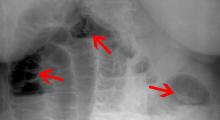

• Röntgenaufnahmen des Bauchraums (Abdomens), evtl. mit Kontrastmittel